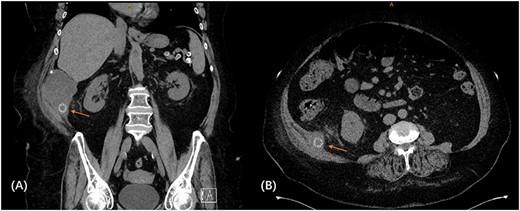

We proceeded with a multiphase computed tomography (CT) scan which was suggestive of a mixed density lesion measuring 62 × 86 × 98 mm arising from the right posterior transverse abdominis/internal oblique muscle, with a well-defined rounded calcific focus at its inferior aspect likely representing a dropped gallstone (GS) associated with abscess formation (Fig. 1). She was commenced on intravenous antibiotics and, in review of her medical comorbidities and DAPT on board, underwent image-guided percutaneous drainage of the gallstone associated abscess collection in the first instance. Following a course of intravenous and oral antibiotics, she was followed up in the outpatient clinic where the drain was removed after 9 days as the output was serous and minimal. Clearance from anaesthetics and cardiology were obtained during pre-operative evaluation of fitness towards surgery, including an ECHO which demonstrated severe left atrial enlargement and moderate mitral stenosis but normal systolic function. DAPT was withhold since initial admission. She underwent an elective procedure 4 weeks later from the initial presentation with pre-operative CT-guided drain localization of the gallstone (Fig. 2) followed by an extra-peritoneal approach of exploration of the right flank. A single 18 × 15 × 14 mm intramuscular gallstone was removed from a deep intramuscular abscess cavity at 6 cm, with fibrous and inflamed tissue surrounding the stone (Fig. 3). Histopathology demonstrated a gallstone with acute inflammation and acellular debris. The postoperative course was uncomplicated with patient discharged on Day 3 post operation and remained well at outpatient follow-up with DAPT restarted.

CT-guided pigtail re-insertion pre-operatively to assist localization of gallstone (A); drain placed in the right subhepatic collection located within the transverse abdominis muscle (B).